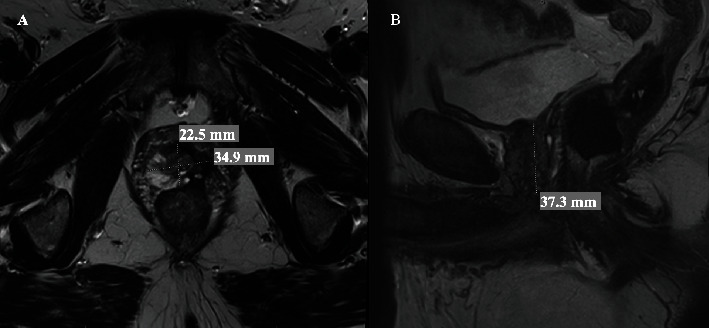

Transperineal prostate biopsy is becoming a popular approach in the diagnosis of prostate cancer. Urethral bleeding and urinary retention are the most common complications. We report a case of intraperitoneal bleeding after transperineal prostate biopsy in a patient with history of focal therapy for prostate cancer. The patient presented with dizziness, abdominal pain, and tenderness a few hours after the procedure. A computed tomography (CT) scan showed intraperitoneal bleeding. He was managed conservatively without needing any interventions or blood transfusion. Intraperitoneal bleeding is a possible, rare, and unexpected complication after transperineal biopsy especially in smaller prostates with prior procedures and scarring.